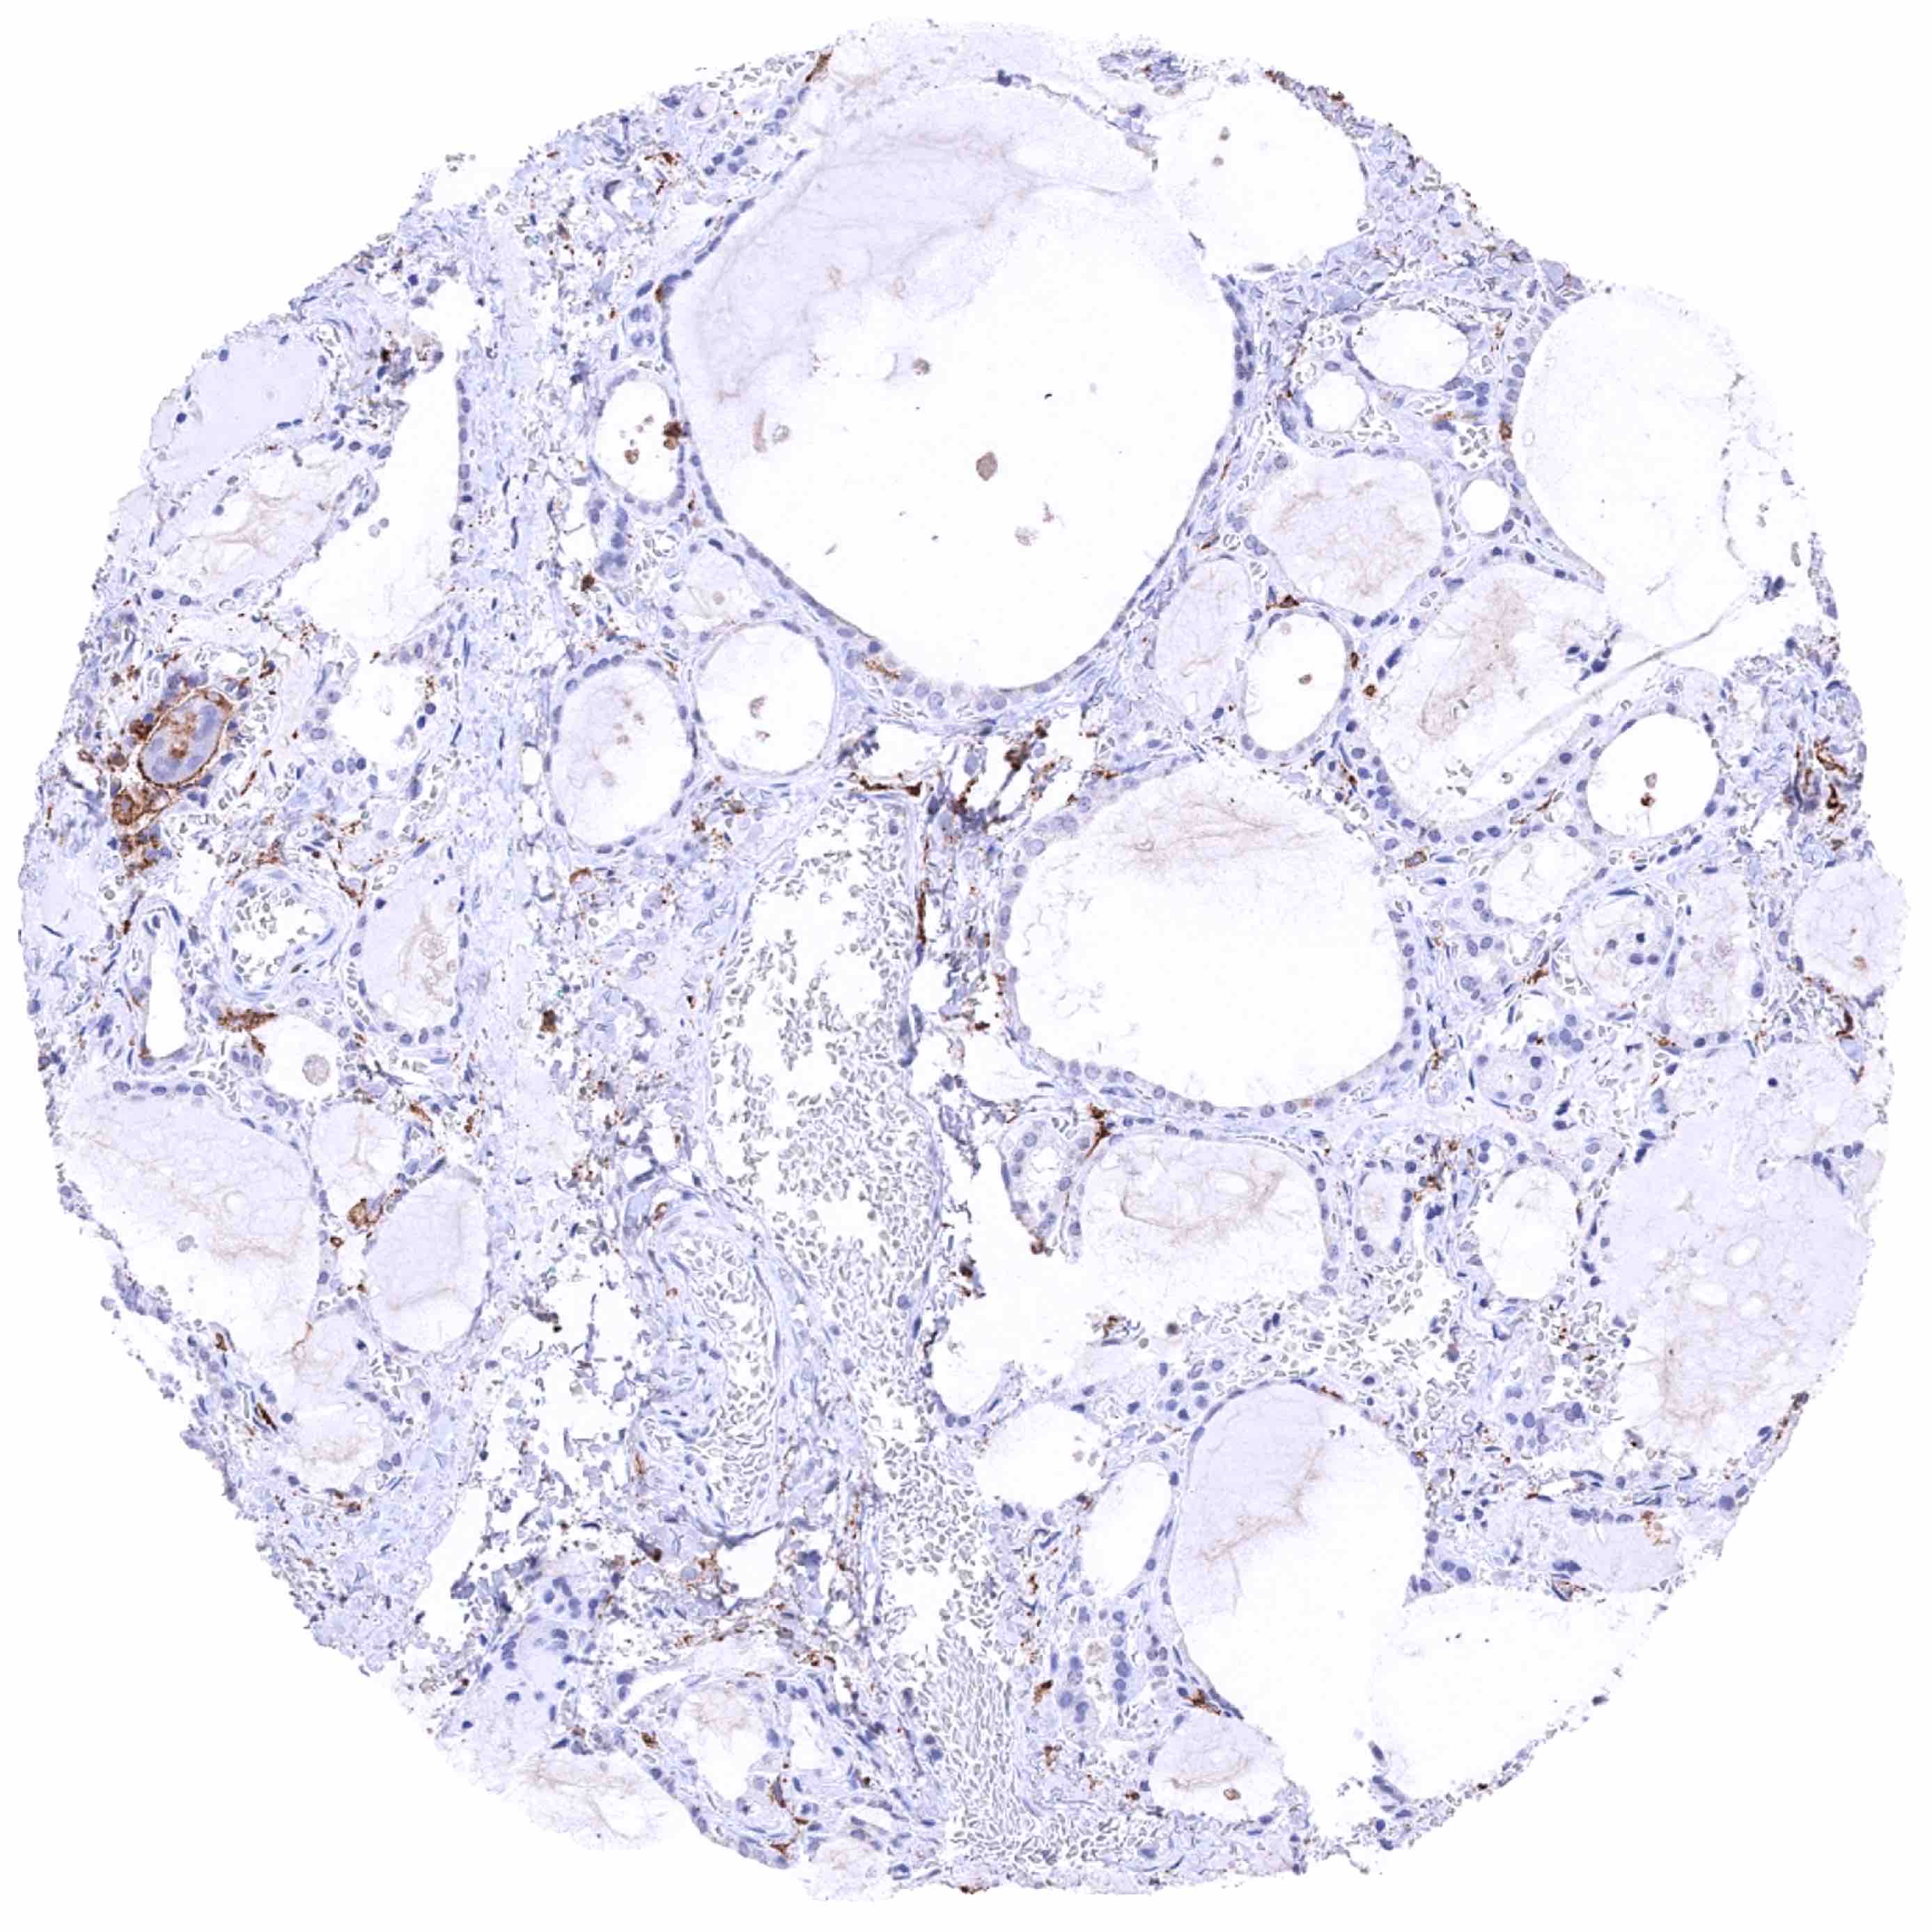

Thyroid gland